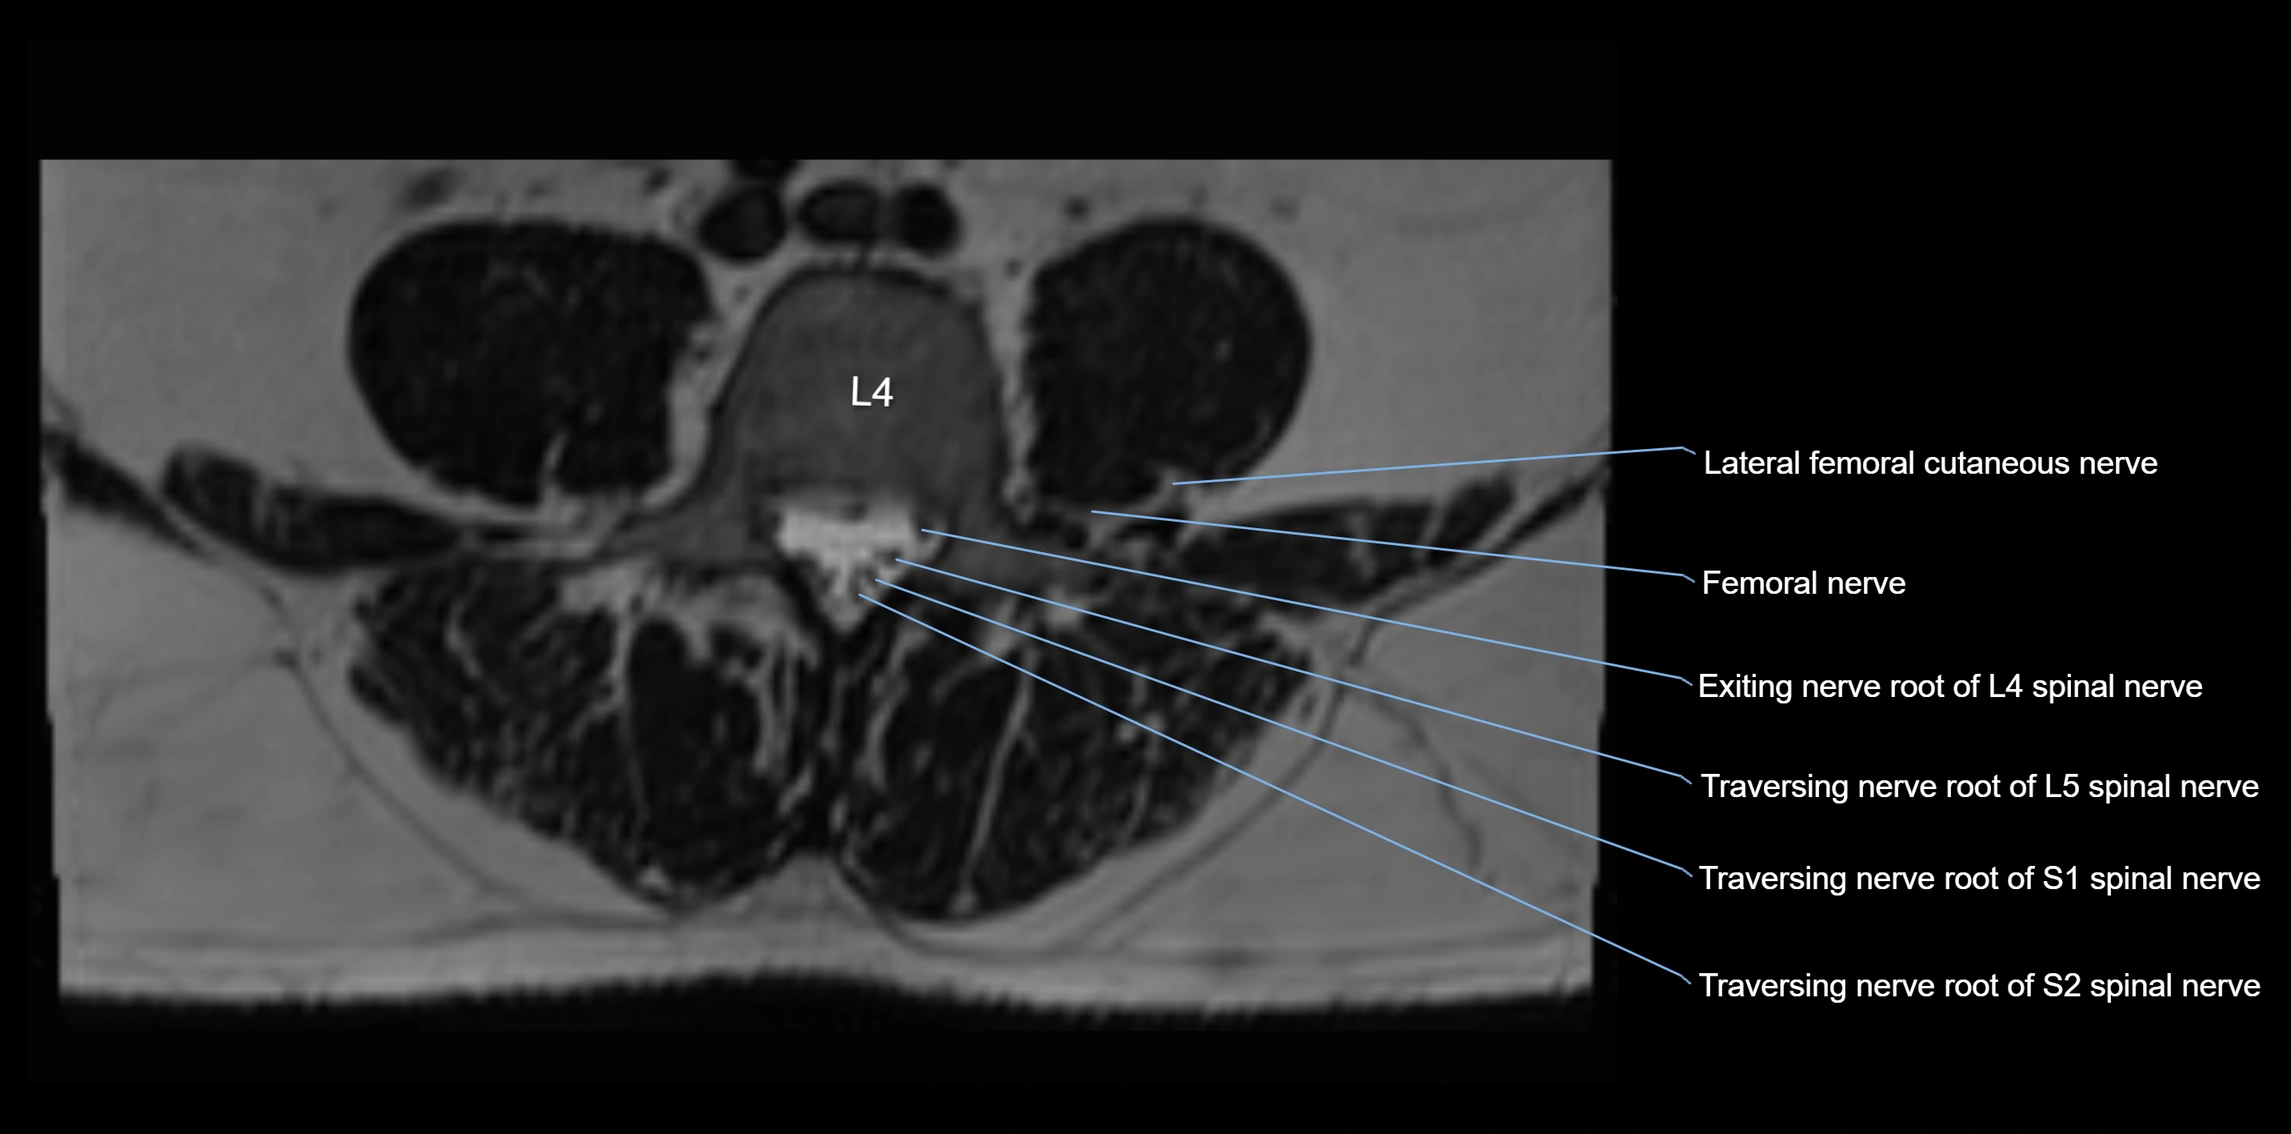

MRI Appearance

T1-weighted images:

• Nerve appears as a very thin low-to-intermediate signal intensity structure

• Surrounded by bright fat, aiding visualization

T2-weighted images:

• Nerve shows intermediate to mildly hyperintense signal compared to muscle

• Pathological involvement appears brighter

STIR (Short Tau Inversion Recovery):

• Normal nerve appears dark

• Inflamed or entrapped nerve appears bright hyperintense

T1 Fat-Sat Post-Contrast:

• Normal nerve enhances minimally

• Pathologic nerve (neuritis, entrapment, tumor infiltration) shows focal or diffuse enhancement

3D T2 SPACE / CISS:

• Nerve appears intermediate to mildly hyperintense compared to muscle

• Surrounded by bright fat or CSF, improving visualization

• Best sequence for mapping small pelvic nerves such as the anococcygeal